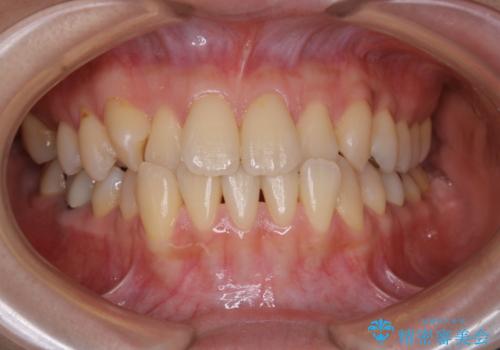

前歯の反対咬合 インビザラインできれいに修正

- 非抜歯 インビザラインによる部分的な反対咬合・ガタつきの改善を計画した。

マウスピース矯正の場合、歯の移動は少しずつ動くよう規定されるため、クロスバイトが乗り越える際非常に咬みづらい時期があります。

しかし、根気強く使っていただく事で、ワイヤーを張ることなくきれいな歯並びとなりました。

歯が折れてしまっていた部分などは矯正前に修復処置をしています。